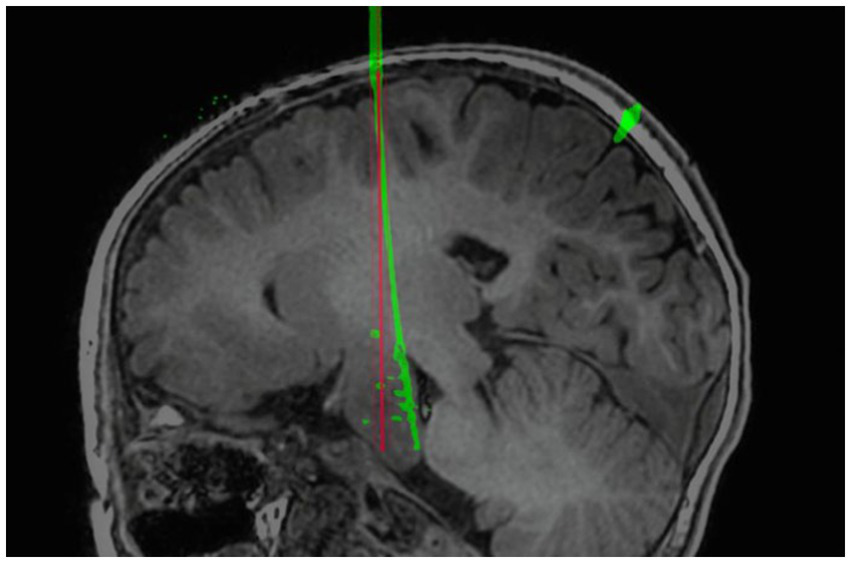

In our multivariate analysis of TPLE, we did find a clear positive correlation between intracranial electrode length, EPLE, and TPLE. This is similar to findings reported by other institutions (27–29, 37). However, van der Loo et al. (29) found that the length of the electrode was not significantly associated with the results and that short electrodes could also show bending immediately after entering the skull, resulting in a large deviation. Indeed, we found that whether or not intracranial electrodes are bent is also significantly related to TPLE. Although the number of electrodes that bend is small, electrode bending often leads to large errors (Figure 5) (27). We performed univariate analysis of factors that may influence electrode bending, but found no statistically significant variables (not listed here). Whether electrode bending is related to factors such as the type of electrode, the structure passed through the skull, etc., needs further research. In our study, we found that most curved electrodes occurred in larger lesions. Nevertheless, from a clinical perspective, these errors did not compromise SEEG recordings because the target was still located in the lesion and electrode bending did not result in complications, so we could still choose the appropriate electric contacts for thermocoagulation.

Figure 5

Example of self-bending of an intracranial electrode. The electrode spontaneously bent in the brain. The red line is the planned electrode track, and the green line is the actual electrode track in postoperative CT after reconstruction.